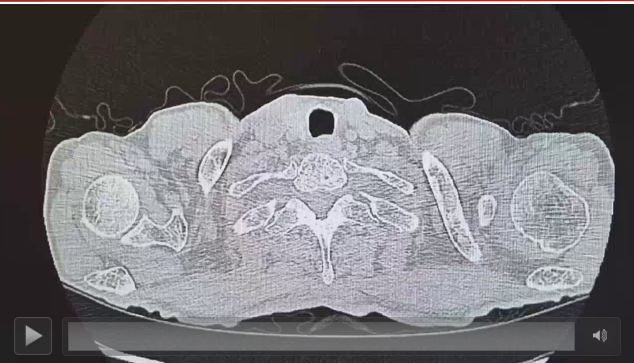

手术方式:2024年11月29日行达芬奇机器人辅助左下肺袖状肺叶切除+纵隔淋巴结清扫术。

5、术后病理与辅助治疗

病理评估:少量鳞状细胞癌残留,达到主要病理缓解(MPR)。

术后分期:ypT1bN0M0 IA2期(成功降期)。

辅助治疗:自2024年12月起,启动纳武利尤单抗单药辅助治疗480mg D1,Q4W 维持1年。

随访:截至2026年3月,术后定期复查CT未见复发转移征象。